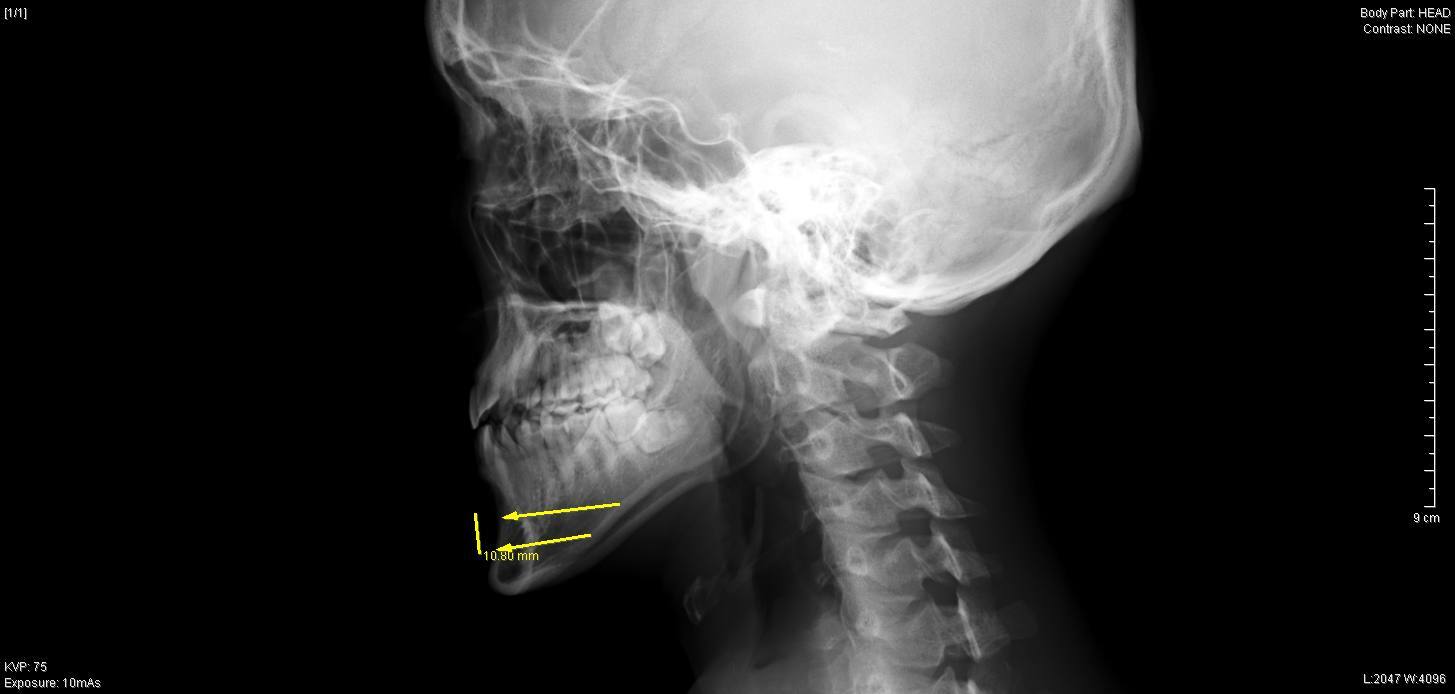

今回の症例では、最大9mm幅で下顎骨を中抜きし、

おとがい先端を約4mm前進させて

チタンスクリュー、プレートで再接合しました。